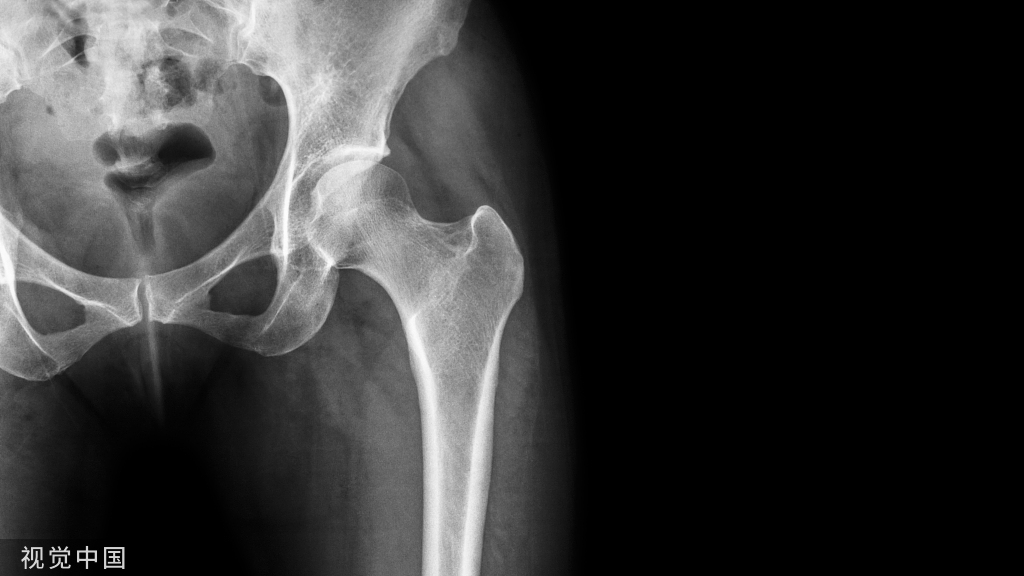

年龄:2岁性别:男病史:O型腿,走路困难

X线

X线见双胫骨内翻,双胫骨近侧干骺端增宽,内侧皮质增厚呈鸟嘴样

结论:Blount病

Blount病(胫骨内翻)是一种累及胫骨近端的进行性畸形,发病机制可能是由于胫骨近侧骺板的内后方受到应力,导致生长板发育障碍。该病分为婴儿型和青少年型。

婴儿型Blount病,常为双侧受累(60~80%),但双侧多不对称。多有家族史,见于1~3岁婴幼儿,危险因素是过早走路和肥胖。需要与生理性弯曲相鉴别。

当临床出现进展性内翻,同时平片中胫骨近端出现特征性改变(干骺端内侧增宽、规则,骨皮质增厚且呈垂直走形呈鸟嘴样;内侧骨骺高度减小)时可以明确诊断。